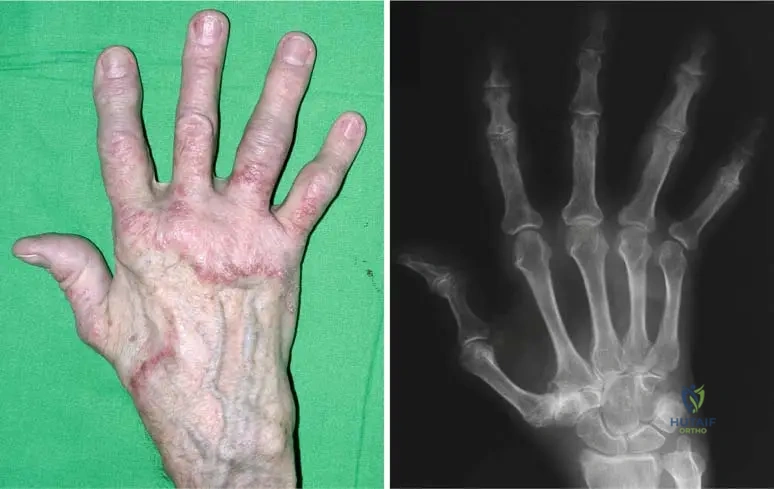

A 15-year-old male presents with a history of easy bruising and skin fragility. On examination, his skin is noted to be remarkably soft and can be stretched significantly beyond normal limits. He also demonstrates excessive range of motion in multiple joints, including his elbows and knees, as shown in the images below. This constellation of findings is most consistent with a disorder primarily affecting which of the following?

Rationale: The clinical features described (easy bruising, skin fragility, skin hyperextensibility, and generalized joint hypermobility) are hallmarks of Ehlers-Danlos Syndrome. The provided text explicitly states that Ehlers-Danlos Syndrome is a "heritable disorder of connective tissue (collagen fibers and mucopolysaccharides)." Therefore, it primarily affects connective tissue. The images further illustrate the excessive mobility of joints, a key feature of connective tissue laxity.

A 32-year-old female presents with chronic joint pain and a history of multiple joint subluxations. On physical examination, she demonstrates the ability to hyperextend her elbows and knees significantly beyond the normal range, as shown in the images. Her skin is also noted to be soft and velvety. These findings are indicative of a generalized disorder characterized by:

Rationale: The vignette describes a patient with chronic joint pain, subluxations, and hyperextensible joints, consistent with Ehlers-Danlos Syndrome. The image further illustrates "Excessive mobility of the joints." The text explicitly lists "generalized joint hypermobility" as a characteristic of Ehlers-Danlos Syndrome. The other options are not consistent with the described clinical picture or the known features of Ehlers-Danlos Syndrome.